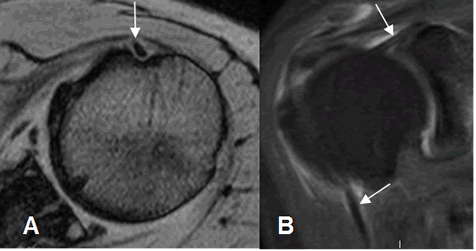

Fig 27. Labrum normal.

A, B, C y D: RM axial en FFE. Distintas configuraciones normales del labrum anterior.

Fig 28. Labrum normal.

A: ArtroRM axial. Rebordes normales anterior y posterior.

B: ArtroRM coronal. Rebordes normales superior e inferior.

C: RM sagital en T2. Labrum adherido a la cavidad glenoidea.

Fig 29. Surco sublabral normal.

ArtroRM coronal. Defecto regular en el labrum superior, que corresponde al surco sublabral.